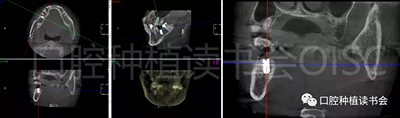

5.3.6 術(shù)后即刻CBCT(美亞光電)檢查種植體軸向及深度良好(圖19)。

圖19 術(shù)后即刻CBCT確認(rèn)種植體頰、

舌側(cè)骨板完整,并保持了足夠的厚度。

5.4.4 種植冠封閉螺絲孔后,調(diào)合,拋光,完成最終修復(fù)(圖27);戴牙前CBCT顯示:種植體頰側(cè)骨板厚度為2.88mm;47種植冠獲得了良好的穿齦輪廓,并維持了正常的頰側(cè)牙弓輪廓。